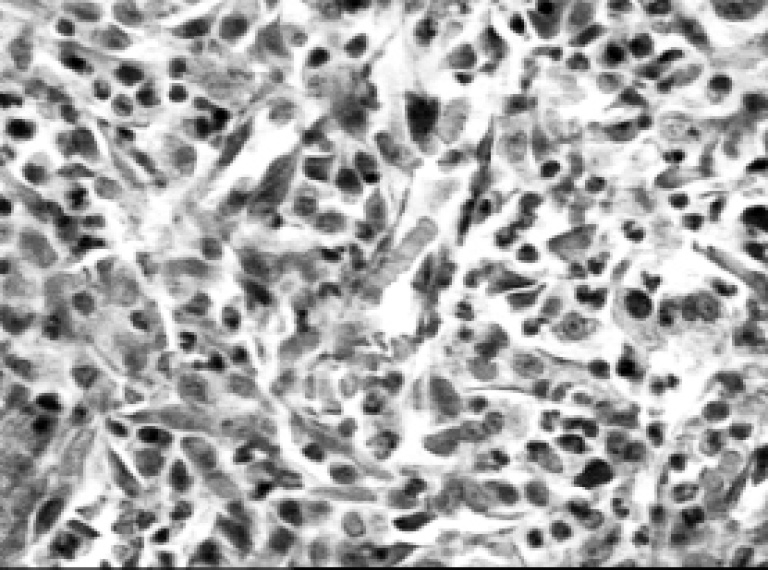

Как следствие, репаративные процессы в ранах были замедлены. При этом формирование грануляционной ткани возле проходящих сосудов мышц и кожи на бедре была более выражено в контрольной группе по сравнению с облученными животными. На 15-е сутки после поражения вокруг кровеносных сосудов отмечены единичные активированные фибробласты. В этих же участках выявлялись малодифференцированные бластоподобные формы мигрирующих клеток и мелкие скопления эндотелиоцитов (по 2–3 клетки) – «почки роста» сосудов, образуя зоны новообразования соединительной ткани, остальные фасциальные участки дна раны были обеднены клеточными элементами. При этом вокруг сосудов фасций на дне раны визуализируются единичные новообразованные капилляры, фибробласты и многочисленные плазматические клетки (рис. 5).

Рис. 5. Микропрепарат мягких тканей в области бедра крысы через 15 суток после РМП. Окраска гематоксилином и эозином, ув. ×250

Через 10 суток грануляции занимали все пространство под струпом, однако зачастую были неполноценными, с небольшим числом клеток, из-за замедленного роста сосудов в ткани формировались бессосудистые зоны. Наблюдалось незначительное количество новообразованных сосудов и мигрирующих клеток в области аркад.

Общая площадь и толщина вновь сформированной грануляционной ткани были в 1,5–2 раза меньше по сравнению с животными контрольной группы.